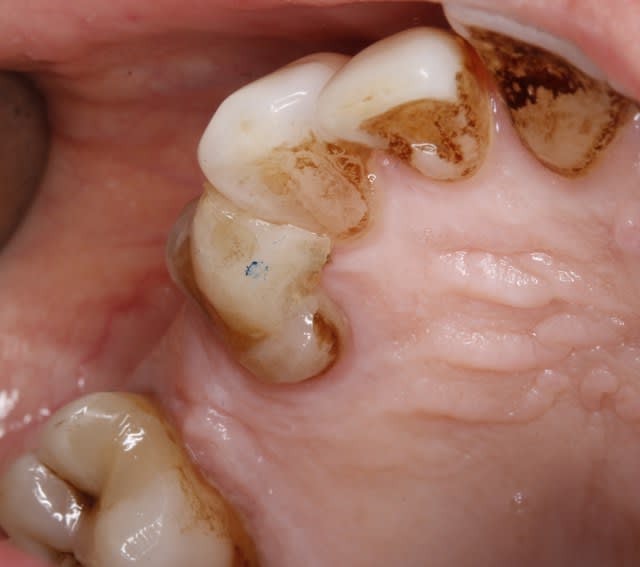

Houlà!c'est du lourd comme tu dis ! Elle a 50 ans cette dame ? Oups, faut la prévenir que son age dentaire est 70 balais et encore ...6 mois me parait raisonnable comme durée de "vie" .... Mais de toute façon , c'est intéressant si la patiente "coopère" ! bises Enlaye

Bon, si ça foire, moi je te l'enlève à l'arrache-couronne!😋